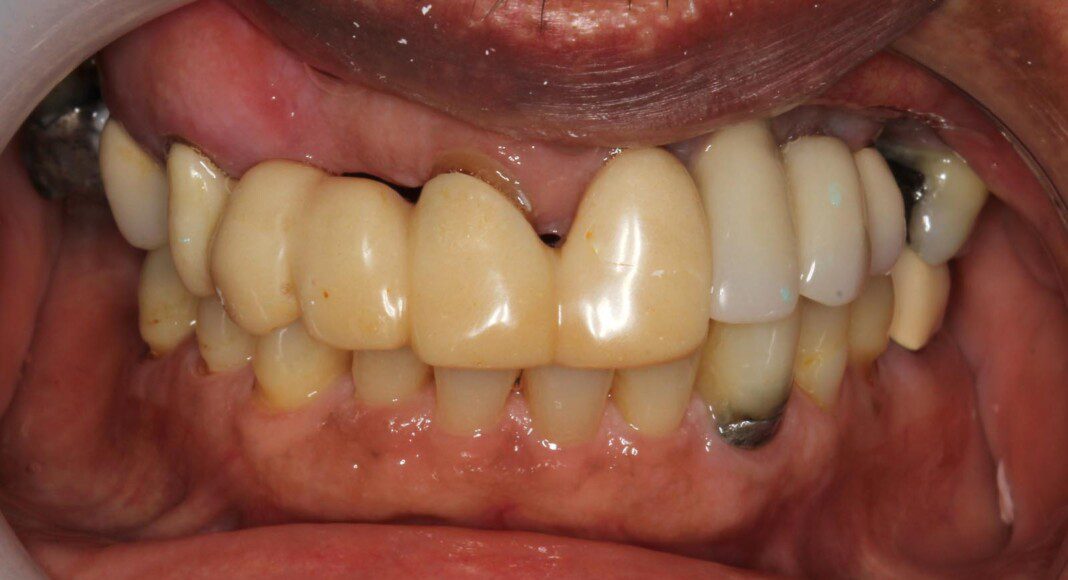

Post-surgical frontal picture. Some new implants were stable enough to place immediate temporary bridge on three new ones and two old ones.